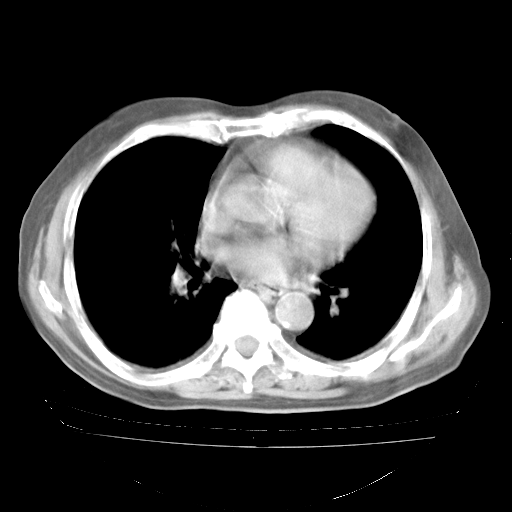

4月28日肺部CT——再次出现类似去年5月9日——透光度降低,“间质性”改变。

4月28日肺部CT——再次出现类似去年5月9日——磨玻璃样、间有“粟粒样”改变。

1、108#的是4月14日的胸部CT(发此贴时还没看着28日的CT)。14日的胸部CT其实已经出现改变(如108#所述),个人认为28日的胸部CT除纵膈窗疑似有双侧胸膜增厚或少量胸积液(可行胸部B超明确)外,与4月14日对照病变有所加重;2、已经给予“异烟肼、利福平、乙胺丁醇”抗痨治疗?如果是,甲强龙80mg可缓慢减量;如果环磷酰胺已停用,暂不使用;3、中性粒细胞92%,明显升高,目前体温情况?注意合并细菌感染可能,使用左氧氟沙星情况下,是否联用B-内酰胺类抗菌药物?另外是查免疫全套非风湿全套。

今请临免主任会诊后认为:4月14日胸部CT已有双下肺间质性改变。患者病情复发多系激素减量过快不正规所致。目前甲强龙80mg/日,一周后酌情开始减量,不易过快。环磷酰胺若已停用,暂不使用。他同意目前抗菌药物使用,但应考虑是否加用B-内酰胺类抗菌药物(中性细胞明显增高);2、结核复发目前依据不足;3、若免疫全套各项指标正常,考虑多系特发性肺间质炎可能大。4、加强支持,并注意保护胃黏膜。

今上午去请教了临免、呼吸主任:1、介绍病史和阅读系列胸部CT一致认为:患者肺结核不考虑,仍为肺间质纤维化,目前处于急性肺泡炎阶段。2、若仍发热,可将甲强龙增至:80mg Bid静滴,同时鉴于中性增高,合并细菌感染可能,继续左氧氟沙星治疗,再联用B-内酰胺抗菌药物,如头孢哌酮--舒巴坦;3、停用抗痨药;4、目前甲强龙每日剂量160mg ,体温正常后再酌情减量;目前暂不用免疫抑制剂;4、不建议使用免疫增强剂等;5、加强支持治疗,鼓励患者进食;5、注意随访肝、肾功及血常规情况;6、因患者目前激素用量较大,加用胃黏膜保护剂,防止消化道出血可能。